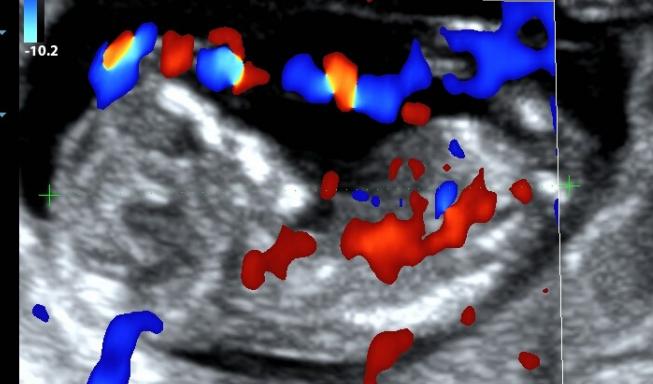

其实早在约6周的时候就可以看到宝宝有节律的心跳了。

除了心跳,我们还能看见TA的整个身体雏形了。